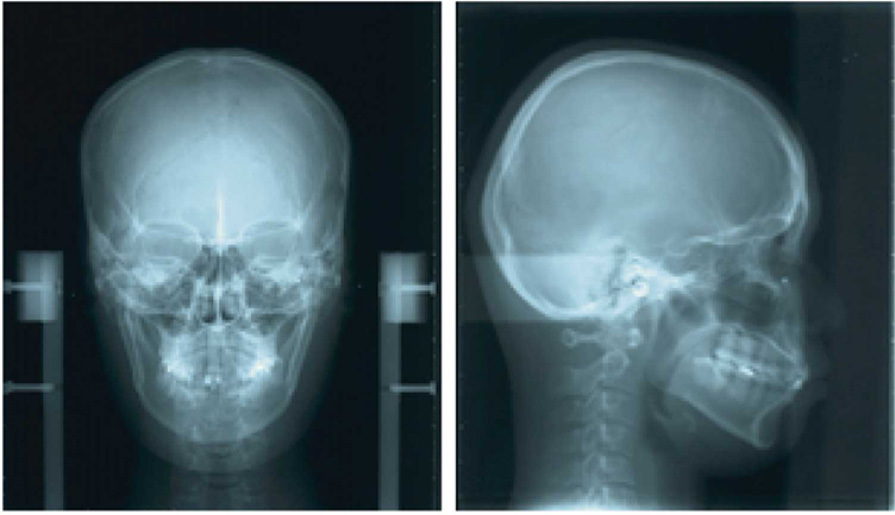

Streszczenie: W leczeniu ortodontycznym dorosłych pacjentów z wadami zgryzu ze współistniejącymi chorobami przyzębia związanymi z urazem okluzyjnym konieczne jest odpowiednie kompleksowe leczenie rekonstrukcyjne. W opisanym przypadku u pacjentki rozpoznano rozległe, przewlekłe zapalenie przyzębia o nasileniu umiarkowanym, związane z urazem okluzyjnym, i poddano ją starannemu leczeniu periodontologicznemu wraz z 20-miesięcznym leczeniem ortodontycznym. Przed aktywnym leczeniem ortodontycznym i po nim dokonano oceny urazu okluzyjnego z wykorzystaniem folii Brux Checker (BC). U pacjentki uzyskano stabilne prowadzenie przednie i funkcjonalne relacje okluzyjne. Za pomocą BC ujawniono związek między zmniejszeniem kontaktów zgryzowych w okluzji bocznej a regeneracją kości. Blaszka zbita była lepiej widoczna, a stan tkanek przyzębia uległ poprawie. Uzyskane przez nas wyniki sugerują, że w przypadku chorób przyzębia związanych z urazem okluzyjnym przeprowadzenie czynnościowej oceny okluzji za pomocą BC oraz badania przyzębia pozwala skutecznie zaplanować leczenie ortodontyczne.